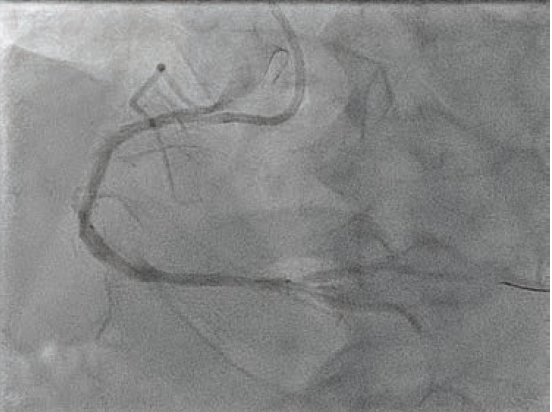

A 6 French AL 0.75 guide catheter was used to engage the ostium of the RCA. A Runthrough® NS Extra Floppy coronary guidewire was placed in the right posterolateral branch, while a Runthrough NS Izanai™ wire coronary guidewire was advanced to the right posterior descending artery (RPDA) as a buddy wire. Initial predilation was attempted with a 2.5 mm x 15 mm NC Euphora™ balloon (Medtronic), but this would not pass the lesion. A 6 French LiquID® guide catheter extension (Seigla Medical) was introduced for additional guide support. Despite this, the 2.5 mm NC Euphora™ was still unable to reach the area of interest without pushing out the guide. A 2.5 mm x 15 mm NC Takeru™ PTCA balloon dilation catheter was used instead, and was successfully brought to the diseased segment and inflated to high pressure. The rest of the proximal and mid vessel was also pre-dilated with the same balloon. We still could not bring the 6 French Opticross™ HD IVUS catheter (Boston Scientific) to the desired area due to the calcific nodule. Therefore, a 2.5 mm x 12 mm C2+ IVL balloon (Shockwave Medical) was used to deliver 70 total pulses to the mid RCA. This was followed by a 3.0 mm x 12 mm C2+ IVL balloon, with which 90 pulses were administered at 4-6 atmospheres (atm) each. Angiography showed reasonable luminal gain (Figure 2).